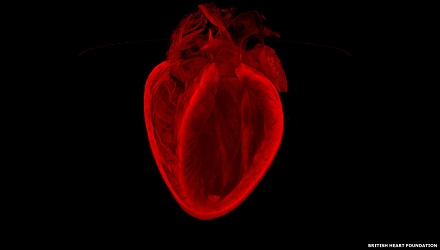

"القلب كما يراه الأطباء"، مجموعة من الصور اخترناها لكم من موقع BBC arabic، بعدما نشرها مجموعة من العلماء البريطانيين، وهي تظهر لقطات مدهشة للقلب وأوعيته الدموية..

الصورة الرابعة: حازت هذه الصورة على أكثر التعليقات، وهي للدكتور وليام مودي من جامعة برمنغهام، وهي صورة قلب لمتبرع بكليته. المسح الضوئي يلتقط أي تغير في حالة القلب عقب التبرع. وهذه التغييرات يمكن علاجها بالأدوية.